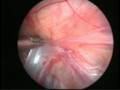

Can this operation be done laparoscopically?

Operation in hydrocele involves closing of the open passage through which the testis has come down. This can be done from outside as in open surgery or from inside by laparoscopy. With the help of laparoscopy we are able to look at the opposite side to see if the passage is open on that side as well. This can be closed at the same sitting if you wish to. Recovery from surgery, timing of surgery and discharge from hospital are the similar for open surgery and laparoscopic surgery.

Laparoscopic repairs have a slightly higher chance of recurrence as compared to open surgery. You can discuss the pros and cons in details with your doctor when you come for consultation.